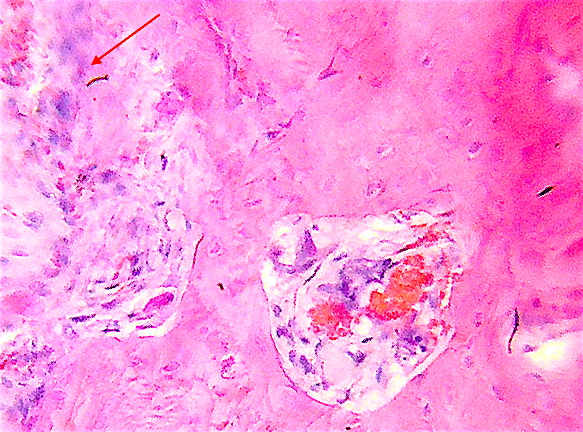

7. Келликер открыл остеокласт в 1870 году

Остеокласт имеет моноцитарно-макрофагальное происхождение линии крови.

Келликер открыл остеокласт в 1870 году; "они выгрызают кость и находят в углублениях".

Это Лакуны Хаушипа или ниши резорбции.

В остеокластах многно отдельных ядер 2-100 и больше.

У старых клеток есть также пикнотические ядра.

Остеобласты слились, чтобы образовать остеокласт.

Это костная клетка! Это открыли Хэм и Фишман.

Скотт и Лак в 1974 году доказали, что это все таки кровяные клетки.

Джи и Ноулен в 1963 году доказали что остеобласт образуется слиянием макрофагов и не является фагоцитарной клеткой.

Это открытие поставило точку.

Исследовали парабиозом - подключали здоровый организм к больному и возникала болезнь «остеопетроз».

Это обусловлено генетическим дефектом стволовых клеток кровянои? системы.